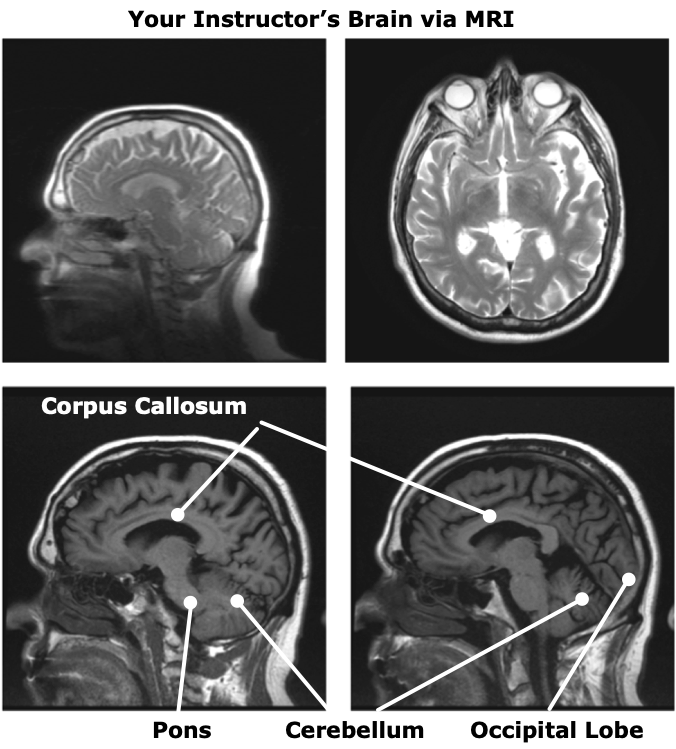

Dr. Joseph P. Hornak (RIT). The Basics of MRI (2003).

[MRI

Image Tumor]

MRI (Magnetic Resonance Imaging).

Whole Brain Atlas (Harvard Medical School)

Hindbrain  Cerebellum

Large, folded structure behind the brainstem.

brainstem = medulla & pons (below)

Pons

("The Bridge")

• Pathway between the Cerebellum and the Cerebrum (see below)

• Connects the Cerebrum above with the brain stem & the spinal cord below.

Deep below the outer cortex, the two hemispheres are connected by a thick bundle of fibers called the corpus callosum

Occipital Lobe

•  Primary visual processing area